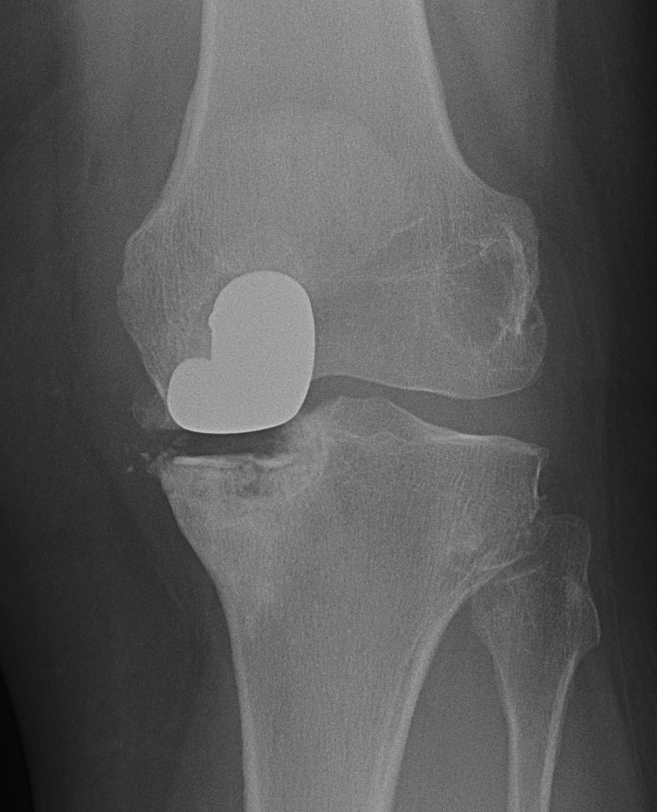

Patient 1